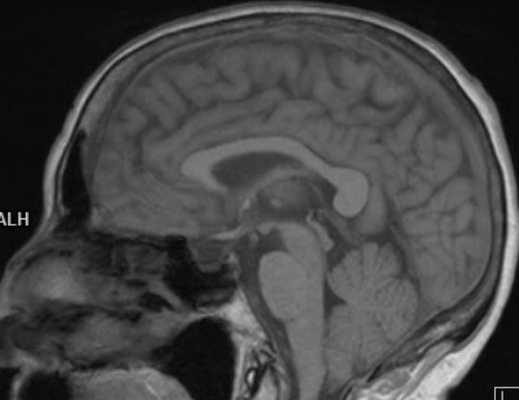

МРТ головного мозга в сагиттальной плоскости. Миндалины мозжечка пролабируют в большое затылочное отверстие (аномалия Арнольда-Киари). Спинной мозг обычной формы и размеров, контуры его ровные, четкие. Структура спинного мозга неоднородная за счет наличия на уровне тел С1-С3 позвонков в зоне сканирования в области центрального канала кистозного включения (сирингогидромиелическая киста). Признаков перифокального отека вещества спинного мозга не выявлено.

- Аномалия Арнольда-Киари. Изменение нормального анатомического положения продолговатого мозга и мозжечка. Врожденный патологический процесс, порок развития. Снимки краниовертебральной зоны позволяют оценить тяжесть расстройства, спланировать лечение.

Это врожденный порок развития, при котором мозжечок и продолговатый мозг расположены атипично (в позвоночном канале).

До появления метода МРТ диагностика данной патологии вызывала большие затруднения, так как другие способы лучевой диагностики не дают четкой визуализации этих структур. В 80% случаев аномалия Арнольда-Киари сочетается с сирингомиелией (множественные кисты в спинном мозге), которая тоже диагностируется только на МРТ.